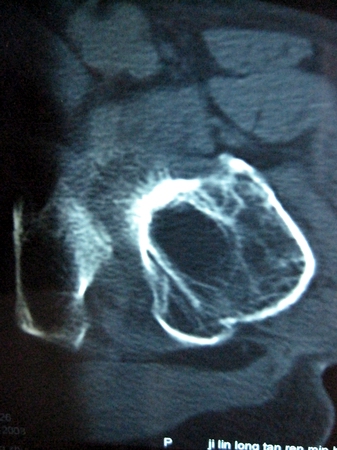

以下是引用lkc8963在2008-12-19 21:19:00的发言:[br]左?右?患侧大转子上移,股骨颈骨质浓杂,髋周见多发条片状骨化影,以小转子为著,多为陈旧性股骨颈骨折后改变并骨化性肌炎.请咨询既往史!